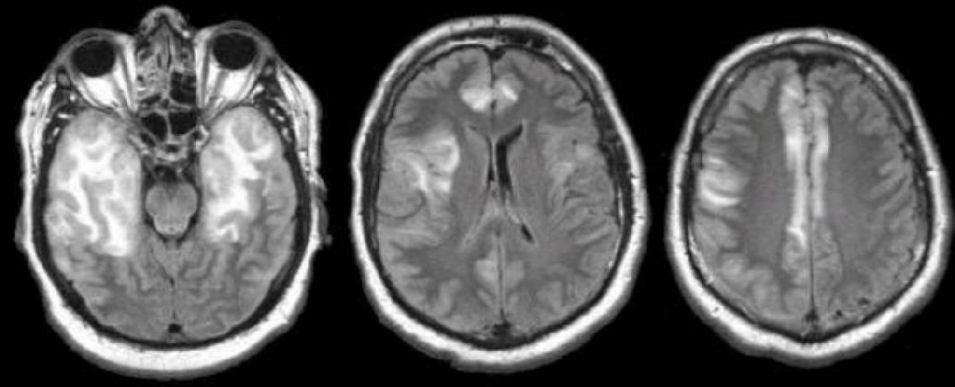

A 38-year-old woman presented to a clinic because of dementia, hemiparesis, ataxia, aphasia, and dysarthria that developed over the last 5 days. She had a 15-year history of intravenous drug abuse and was treated for fever, cough, and shortness of breath before the onset of neurological symptoms. Her MRI shows multiple white matter lesions, as seen in the picture. Over the course of 2 weeks, the patient's condition worsens. Despite aggressive treatment, she lapses into a coma and dies. At autopsy, histologic examination of her brain tissue reveals gigantic, deformed astrocytes and oligodendrocytes with abnormal nuclei. Which of the following is the most likely cause of this woman's neurological symptoms?